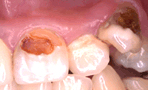

레진으로 치료 후 심미적으로 우수한 모습

레진으로 치료 후 심미적으로 우수한 모습 레진은 전에는 시술 후에 떨어져 나가는 경우가 많아서 잘 쓰이지 않았지만 요즘은 잘 떨어져 나가지 않고 색깔도 치아와 같은 색깔이기 때문에 보기 좋은 장점이 있어서 많이 쓰이기 시작했습니다.